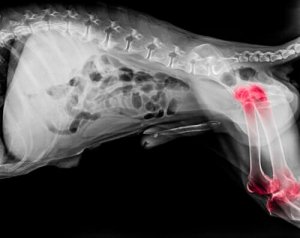

Em geral, pode-se dizer que a artrite é uma doença degenerativa que causa a inflamação das articulações, tanto dos cotovelos quanto dos joelhos.